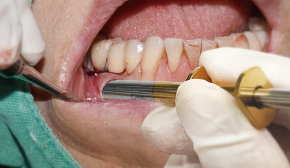

터널 테크닉 시 : 터널 내부에 박리 된 공간으로 깊숙이 골이식재 전달

4. Bone Carrier를 골이식부에 삽입

4. Bone Carrier를 터널 공간에 삽입

-

5. 터널 공간에 골이식재 주입